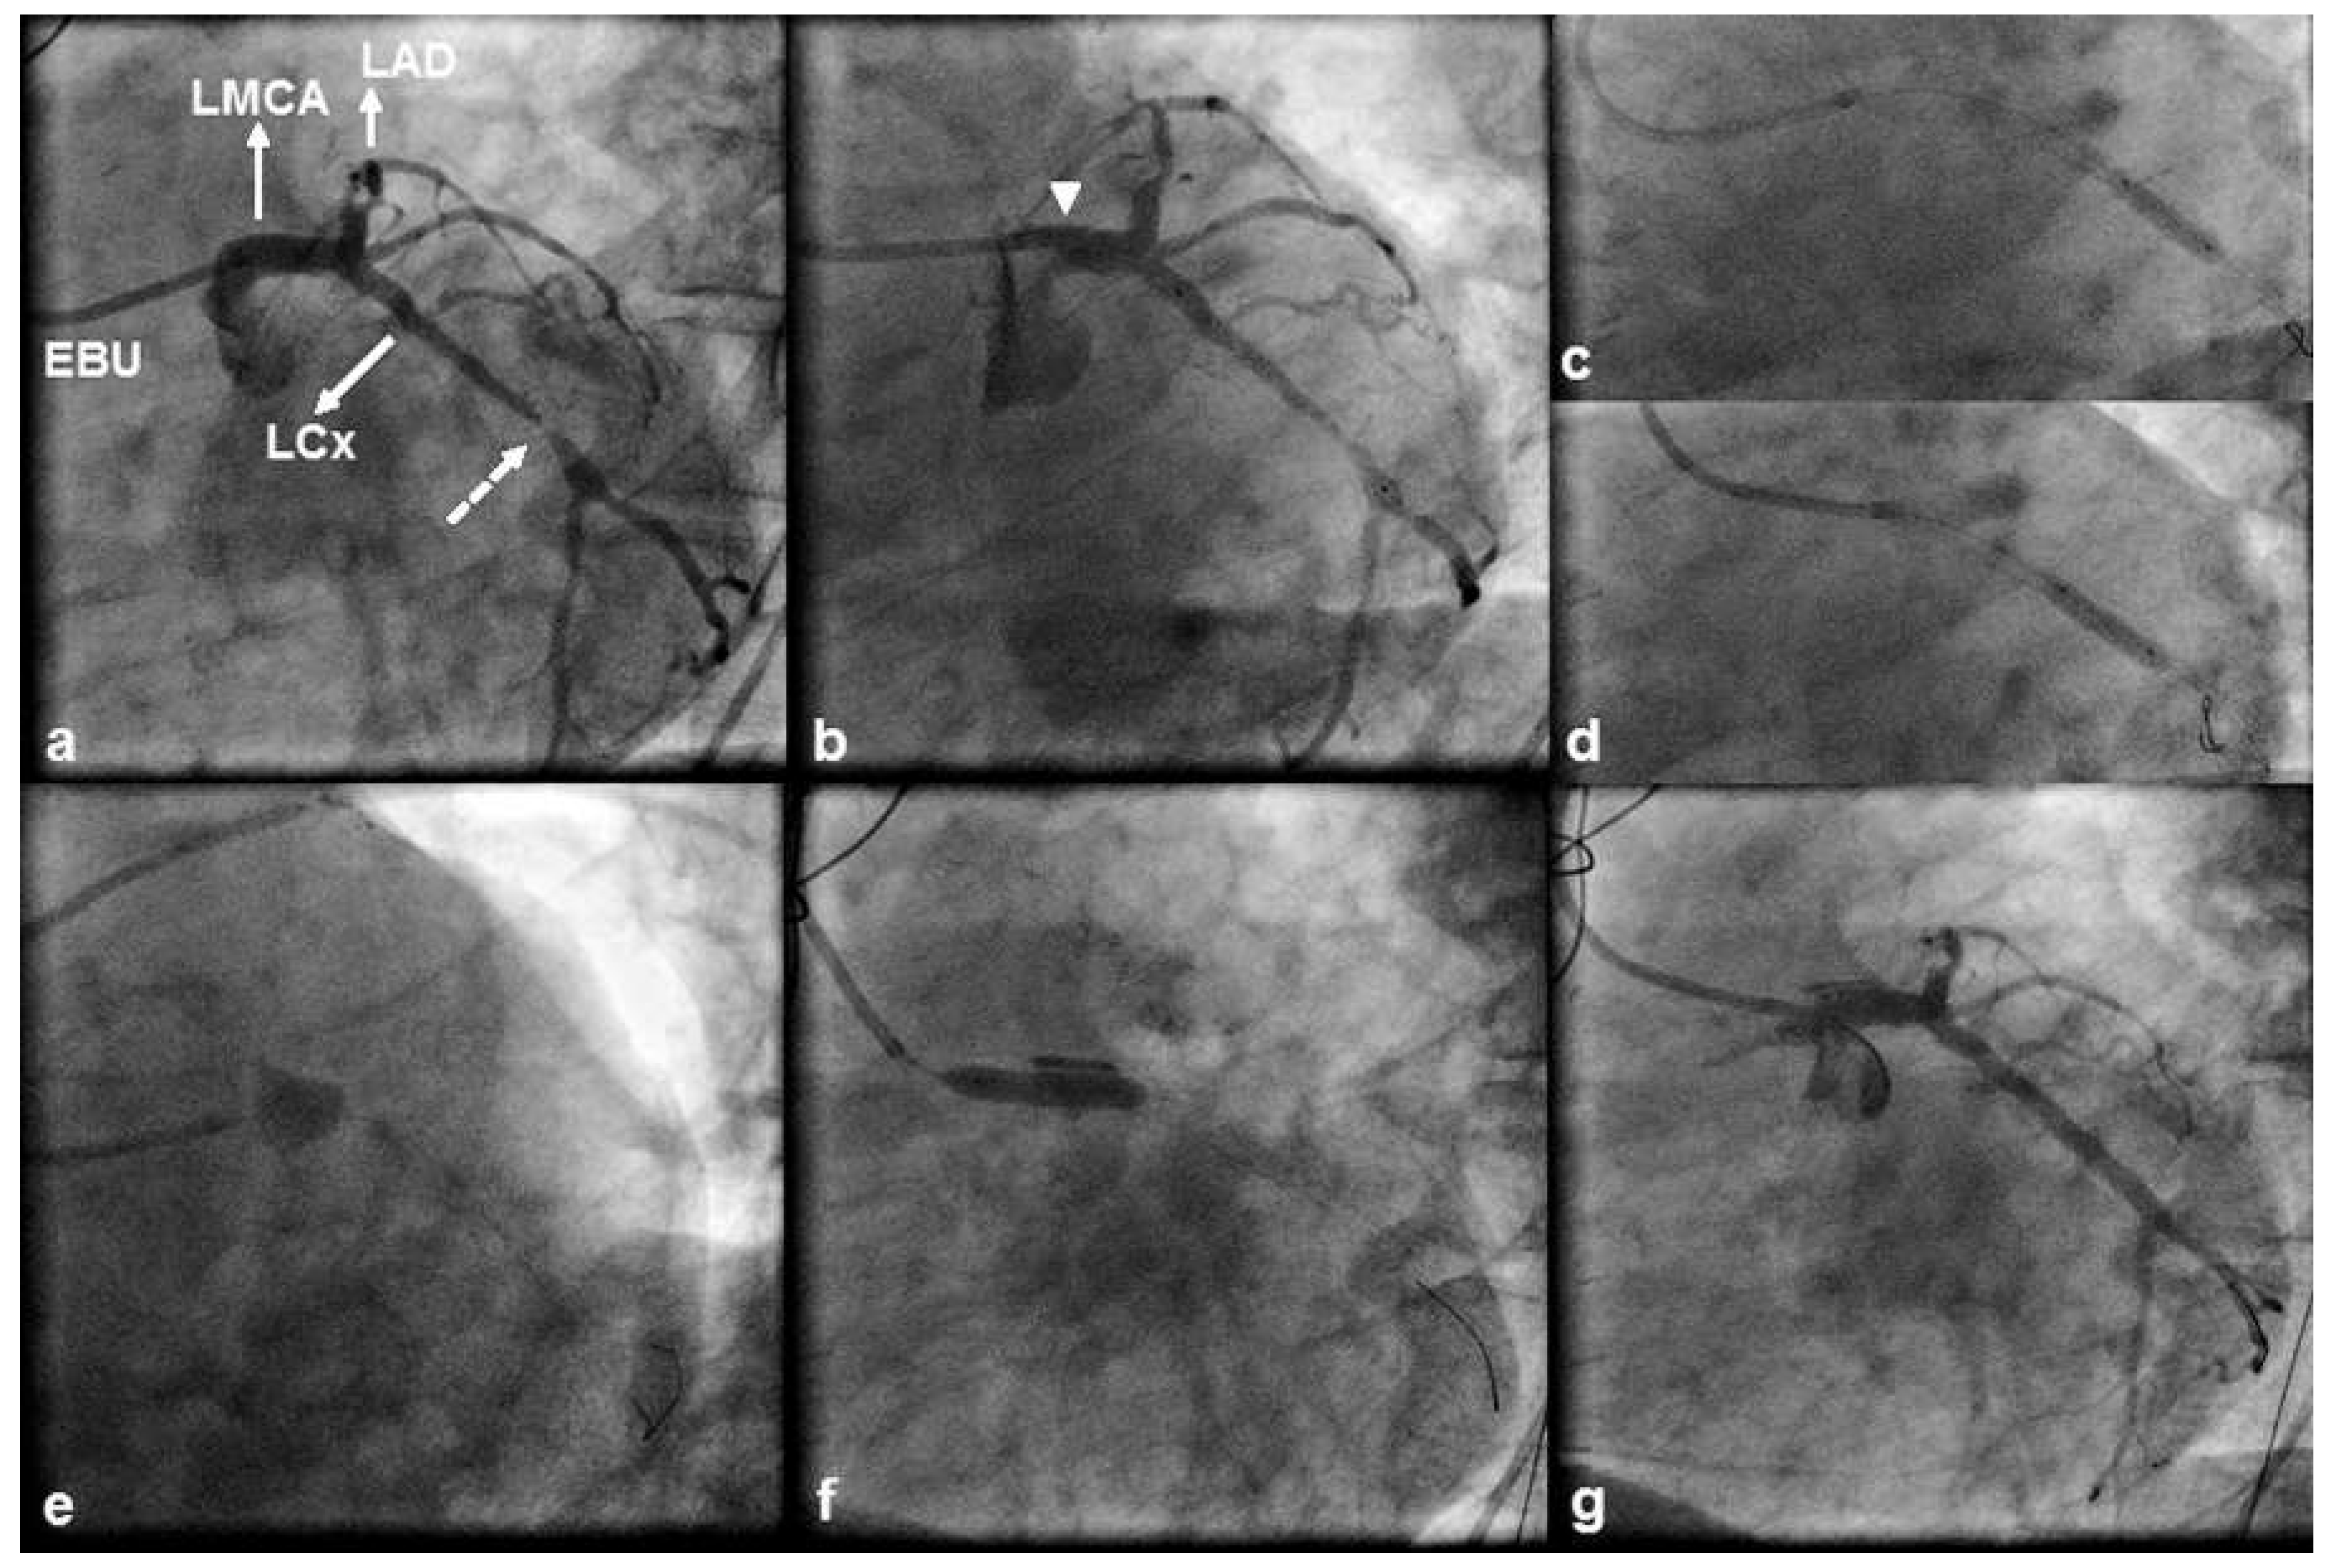

Case 1

A 71 year old, male patient was referred for coronary angiography because of non ST segment elevation myocardial infarction. The echocardiogram performed at the referring hospital showed hypokinesia of the inferior, inferior septal and lateral left ventricular walls with an ejection fraction of 40%. The patient had a history of hypertension, hyperlipidaemia, inferior myocardial infarction and bare metal stent facilitated PCI of a dominant right coronary artery (RCA) and the proximal and distal left circumflex (LCx) artery. In 2011, he underwent CABG with a left internal mammary artery graft to the left anterior descending (LAD) artery and a saphenous vein graft to a diagonal artery; preoperatively, no significant viability was documented with low dose dobutamine echocardiography over the dependent myocardium of the chronically occluded, yet collateralised RCA demonstrated during angiography. Transfemoral angiography during the current admission revealed patent grafts and obstructive in stent disease of the proximal LCx artery culminating in a tight lesion just distal to the outflow of the stent (Figure 1a). Therefore, we proceeded with PCI to the LCx artery. The LMCA was engaged without difficulty with a 6 French Extra Back up (EBU) 4.0 guiding catheter and, after predilation, a 3.5 × 33 mm DES was uneventfully deployed across the lesion (Figure 1b). Because of stent underexpansion at the site of the tight lesion we successfully performed postdilation with use of a 3.75 × 15 mm noncompliant balloon (Figure 1c). A second postdilation was then performed at a more proximal location (Figure 1d), yet subsequent angiography revealed persistent contrast staining outside the coronary lumen at the site of the LMCA ostium, which was compatible with a type C coronary dissection (Figure 1e). The patient was pain free and haemodynamically stable without electrocardiographic evidence of ischaemia. The dissection was immediately tackled with a 4.5 × 18 mm DES (Figure 1f). Postdilation was carried out with a 5.0 × 15 mm noncompliant balloon and final angiography showed complete sealing of the dissection flap (Figure 1g). Postprocedural creatine kinase and creatine kinase MB isoenzyme levels were normal. The patient had an uneventful 2 day hospital course and was discharged home on life long dual antiplatelet therapy. He remained stable 3.5 years post stenting with Canadian angina class I and no evidence of a cardiovascular event.

Figure 1. (a) 45° left anterior oblique (LAO) view of the left coronary artery displaying a tight left circumflex (LCx) artery lesion (dashed arrow) located just distal to a previously implanted bare metal stent. A 6 French Extra Back-up (EBU) 4 guiding catheter is seen engaged in the ostium of a minimally diseased left main coronary artery (LMCA). The left anterior descending (LAD) artery, which contains a mid segment occlusion, is also shown. (b) LAO angiogram showing the stent deployment position. Note the unfavourable position of the guiding catheter resulting in the tip abutting against the wall of the LMCA ostium (arrow). Compared with its position during the first postdilation (c), the tip of the guiding catheter was too deep-seated during the sec- ond postdilation (d). (e) 40° LAO and 40° caudal view depicting persistent extraluminal contrast staining at the site of the LMCA ostium (type C coronary dissection). (f) Stent deployment across the dissection. (g) 45° LAO view showing an optimal angio- graphic result with complete sealing of the dissection flap.